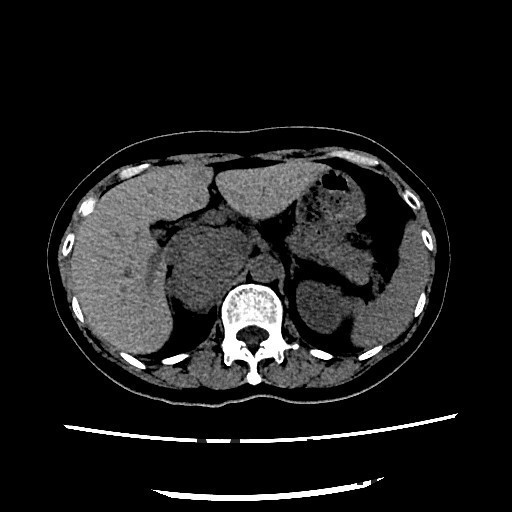

查体:血压:152/80mmHg。双肾区无红肿、隆起,双肾区叩击痛(-),双侧肋脊点、肋腰点压痛(-)。 辅查:CT平扫+增强扫描示:右侧膈下肾上腺区和左侧腰大肌病灶, 考虑为良性肿瘤,嗜铬细胞瘤可能性大,未除外其他

随访:病理回报示:嗜铬细胞瘤。 讨论:该例嗜铬细胞瘤具有较典型的影像表现,我们能看到右侧肾上腺椭圆形肿块,边界清楚,直径较大,这可区别于肾上腺腺瘤,后者一般小于2cm。增强扫描肿块明显强化,并可见无强化低密度区,可能是肿瘤常坏死或陈旧性出血引起。而且该患者有嗜铬细胞瘤引起的继发性高血压,不过追问病史没有典型的阵发性高血压发作。